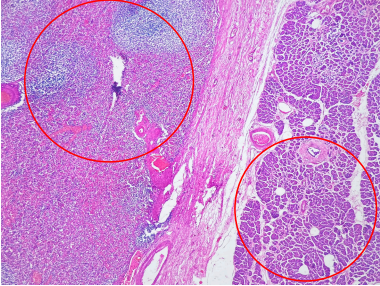

Dada la sospecha diagnóstica clínica e imagenológica se decidió realizar pancreatectomía parcial distal. En el servicio de Patología del Hospital Universitario del Valle, en Cali, Colombia, se recibió la pieza quirúrgica de características externas usuales; al corte, se reconoció un área bien delimitada, redondeada y rojiza, de 6 cm de diámetro mayor, ubicada en la cola del páncreas (Figura 2). Los cortes histológicos mostraron un tejido vascularizado dispuesto en cordones de células con núcleos eucrómicos, redondas y de contornos bien definidos; dentro de los cordones había células inflamatorias mixtas maduras (macrófagos, linfocitos, neutrófilos, eosinófilos y plasmocitos). Los espacios intercordones correspondían a senos repletos de glóbulos rojos y se identificaron nódulos linfoides secundarios rodeando vasos pequeños. El parénquima pancreático adyacente no presentaba alteraciones (Figura 3). Se realizó estudio de inmunohistoquímica donde se evidenció tejido esplénico con pulpa blanca positiva para los marcadores CD20+, CD21+, CD45+, y la pulpa roja positiva para CD8+. En el tejido no hubo inmunorreactividad para CD56, Cromogranina y Sinaptofisina (Figura 4).

Para confirmar el diagnóstico, la biopsia o el estudio en el espécimen de resección puede requerir más allá de la coloración básica de hematoxilina y eosina, la realización de pruebas de inmunohistoquímica. La inmunotinción con CD8 permite identificar las células que revisten los espacios vasculares (pulpa roja), células que a su vez son negativas para marcadores endoteliales y CD45. La positividad de CD45, CD20 y CD21 demarcan las células que constituyen la pulpa blanca.